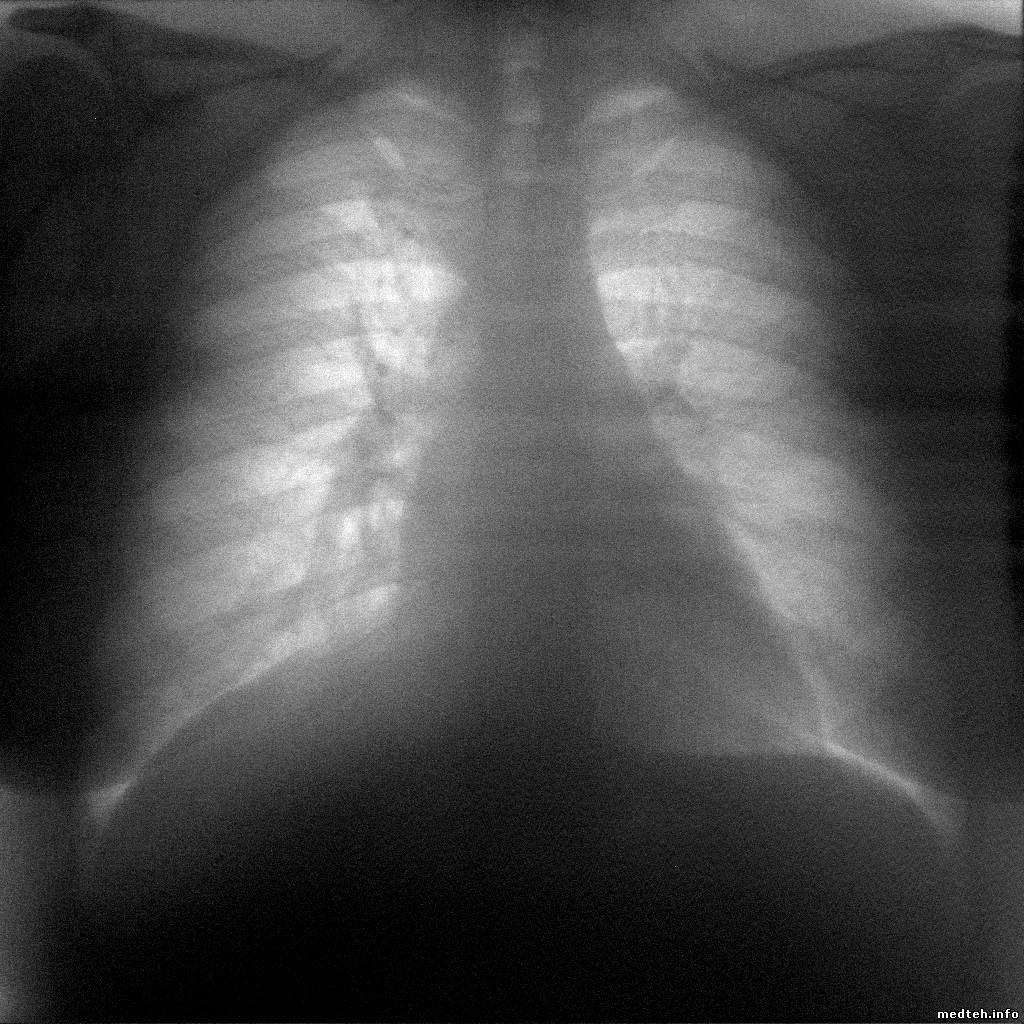

Высоковольтные провода. (Они уже достали). "УРАЛРЕНТГЕН" изготовил их хитрого вида. На одном конце стандартный разъём, а на другом евро. И похоже этот евро штекер они делают сами. В течении гарантийного срока буду заменять уже ТРЕТИЙ высоковольтник. (Хотя техника эксплуатируется в щадящем режиме. Всего около 4500 снимков) Вопрос на сообразительность: возможна ли замена гнёзд в питающем устройстве вместо евро на обычные? Со стандартными проводами проблем, я думаю, будет меньше. Сегодня сделал снимки... 80 кВ 8.0 мАс. снимок с эффектом "снежной бури". Идёт пробив высоковольтных проводов. Дальше поднимать киловольтаж не имеет смысла "снежная буря" усиливается, информативность снимка сводится к нулю.

Образцы снимков:

7559550.jpg (788.8 Kb)